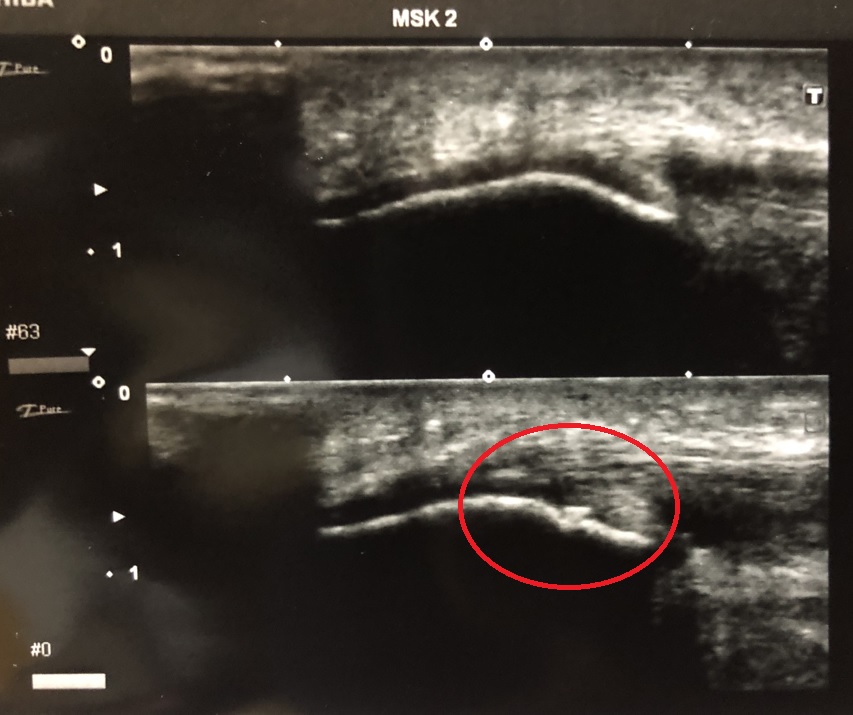

患者情報は、右膝部の痛みを訴えて来院。17歳男子、高校野球部、178㎝/75㎏、既往歴半年ほど前、右膝蓋腱炎(当院受診)であった。

奥田院長が、超音波エコー観察検査を実施。写真にあるように骨折が確認され、野球のトレーニングによる、右脛骨疲労骨折の疑いありと判断。1か月ほどの安 静と運動禁止、のちに野球運動フォームの修正と改善に向けて指導を行うとの事。

静と運動禁止、のちに野球運動フォームの修正と改善に向けて指導を行うとの事。